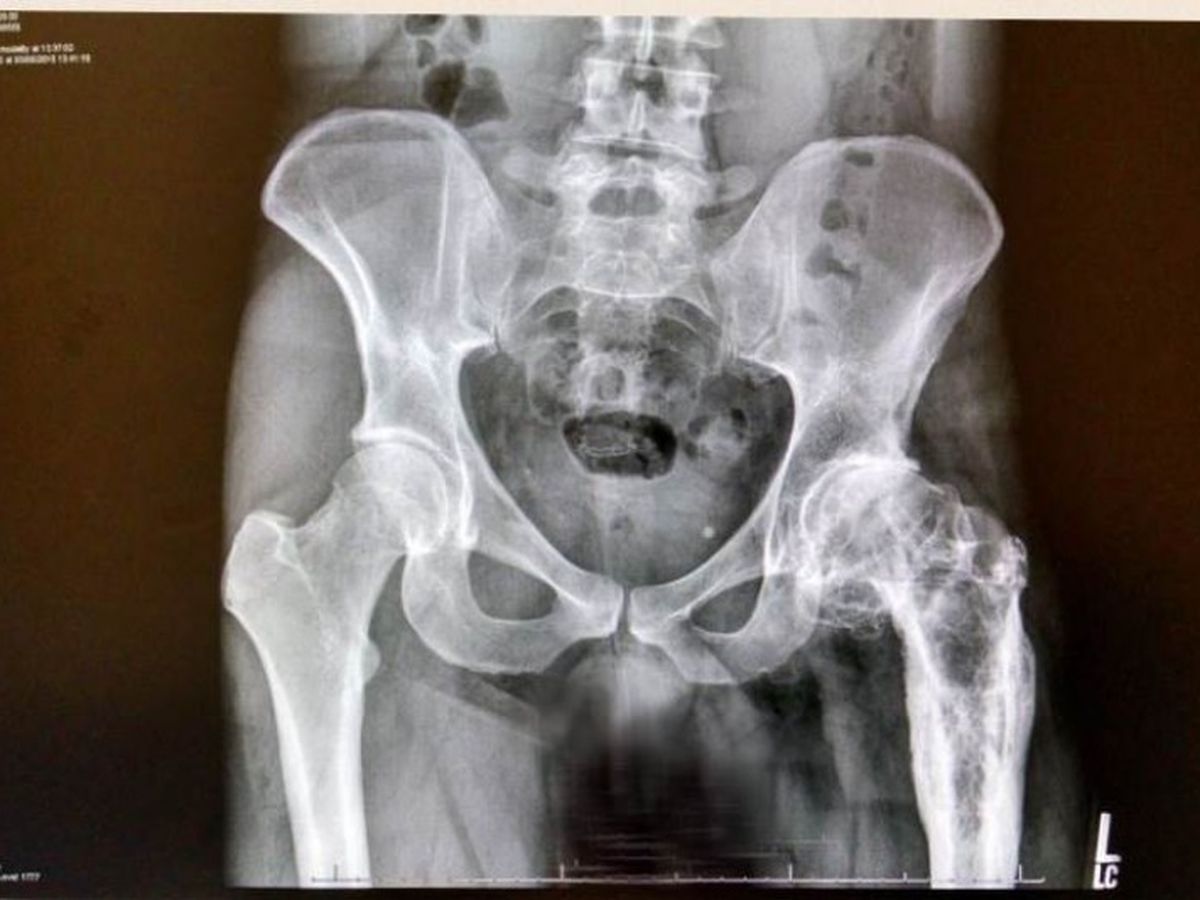

Having dealt with a degenerative hip disease his whole life, Gabe Lenox’s new X-rays shocked the surgeons with the amount of scarring and deformity they revealed. At age 35, he needs a hip replacement.